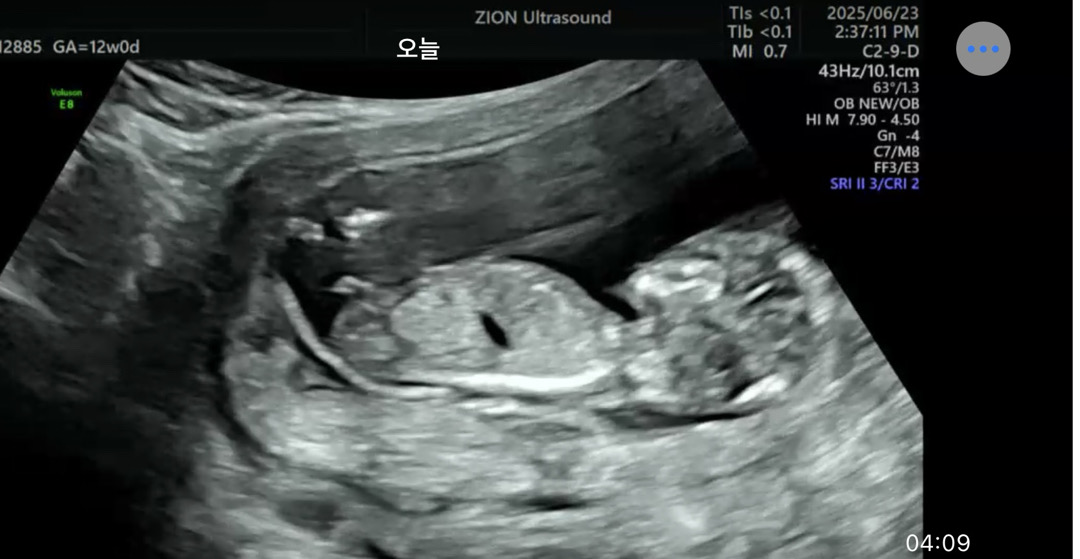

각도법 딸같지 않나요..ㅎㅎ

제눈에는 딸같은데 여러분은 어떠세요~?